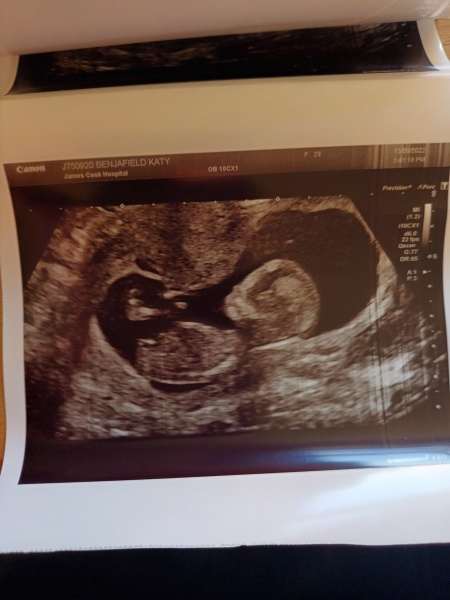

FirstTimeTryer93 · 07/10/2022 10:27

Hi ladies, can I join? 🥰

I am pregnant with our first baby, we have our private gender scan tomorrow. Any guesses please? This scan is from 13 weeks xxx

@FirstTimeTryer93 Congratulations! I would say thats a girl.... although I have absolutely no idea why 😂

I'm gonna say a boy